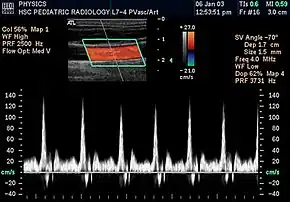

Spectral duplex scan of the common carotid artery

Duplex ultrasonography sometimes refers to Doppler ultrasonography or spectral Doppler ultrasonography.[3] Doppler ultrasonography consists of two components: brightness mode (B-mode) showing anatomy of the organs, and Doppler mode (showing blood flow) superimposed on the B-mode. Meanwhile, spectral Doppler ultrasonography consists of three components: B-mode, Doppler mode, and spectral waveform displayed at the lower half of the image. Therefore, "duplex ultrasonography" is a misnomer for spectral Doppler ultrasonography, and more exact name should be "triplex ultrasonography".[3]

Duplex scan of the common carotid artery

Colour Doppler shows the direction of the blood flow in red or blue (either towards or away from the transducer). Meanwhile, spectral Doppler not only shows the direction of blood flow, it also shows the phases (pulsatility) and acceleration of the blood flow. Any sudden changes in direction of blood flow produces audible sounds on the ultrasound machine.[3]

In spectral Doppler, the y-axis shows the direction and velocity of the flow. Meanwhile, the x-axis (as known as "baseline") shows the flow over time. The gradient at any point on the waveform would therefore shows the acceleration of the flow. In "antegrade" flow, the blood flows according to the normal flow within the circulatory system (e.g. veins flow towards the heart while arteries flows away from the heart). In "retrograde" flow, the flow would reverse (e.g. veins flow away from heart or arteries flow towards the heart). However, "retrograde" flow can be both abnormal or normal. For example, in portal hypertension, there is an abnormal portal venous flow where it flows away from the liver (hepatofugal flow) instead of the normal flow towards liver (hepatopetal flow). In jugular venous pressure waveform of the internal jugular vein, the retrograde "a" waveform is a normal flow due to right atrium contraction. Both antegrade or retrograde flow can be either towards or away from the probe transducer, depending on the position of the probe relative to the blood flow. Blood flow toward the transducer would appear above the baseline while blood flows away from the transducer will appear below the baseline. Waveform of the flow can be classified as: pulsatile (as in arteries), phasic (as in veins), non-phasic (as in diseased veins), and aphasic (no flow). Spectral broadening (thickness of the waveform) increases from large vessels (plug flow) to medium vessels (laminar flow) to small/stenotic/diseased vessels (turbulent flow) due to a larger variety of blood with different ranges of velocities in those with turbulent flow.[3]

Renal ultrasonography using duplex technique of a normal adult kidney, with the estimation of the systolic velocity (Vs), the diastolic velocity (Vd), acceleration time (AoAT), systolic acceleration (Ao Accel) and resistive index (RI). Red and blue colors in the color box represent flow towards and away from the transducer, respectively. The spectrogram below the B-mode image shows flow velocity (m/s) against time (s) obtained within the range gate. The small flash icons on the spectrogram represent initiation of the flow measurement.

Doppler ultrasonography is widely used in renal ultrasonography. Renal vessels are easily depicted by the color Doppler technique in order to evaluate perfusion. Applying spectral Doppler to the renal artery and selected interlobular arteries, peak systolic velocities, resistive index, and acceleration curves can be estimated (Figure 4) (e.g., peak systolic velocity of the renal artery above 180 cm/s is a predictor of renal artery stenosis of more than 60%, and a resistive index, which is a calculated from peak systolic and end systolic velocity, above 0.70 is indicative of abnormal renovascular resistance).[12]